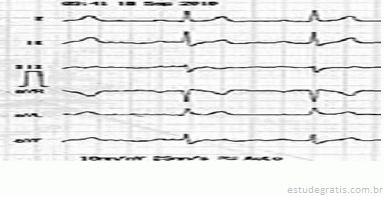

Paciente, sexo masculino, 45 anos de idade, sem patologia

Paciente, sexo masculino, 45 anos de idade, sem patologias prévias, totalmente assintomático, sem histórico familiar positivo para quaisquer patologias cardiovasculares, foi ao médico, pois estava com uma hérnia inguinal. Seu médico solicitou um eletrocardiograma, apresentado em seguida.

Com base nesse caso clínico, e considerando os conhecimentos médicos a ele relacionados, julgue os itens a seguir.